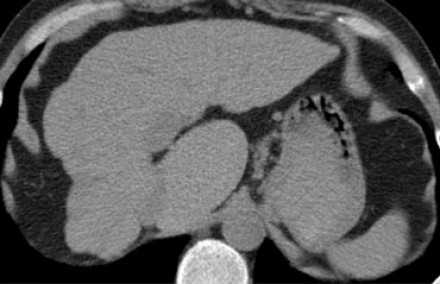

Этот КТ пациента с циррозом печени с атрофией правой доли, с нормальным объемом левой доли и компенсаторной гипертрофией хвостатой доле. Изображение представлено ниже.